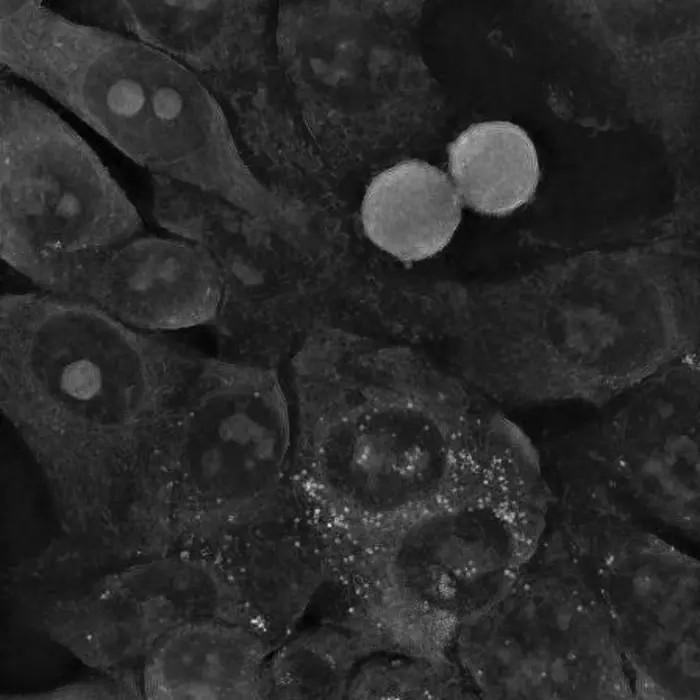

Colon cancer cells after interaction with small spherical gold nanoparticles did not change their morphology and are still able to divide. (Source: IFJ PAN)

The unique features of holotomography allowed the physicists to determine the causes of the unexpected behaviour of cancer cells in the presence of gold nanoparticles. A series of experiments was conducted on three cell lines: two glioma and one colon. Amongst others, it was observed that although the small, spherical nanoparticles easily penetrated the cancer cells, the cells regenerated and even started to divide again, despite the initial stress. In the case of colon cancer cells, the gold nanoparticles were quickly pushed out of them. The situation was different for the large star-shaped nanoparticles. Their sharp tips perforated the cell membranes, most likely resulting in increasing oxidative stress inside the cells. When these cells could no longer cope with repairing the increasing damage, the mechanism of apoptosis, or programmed death, was triggered.